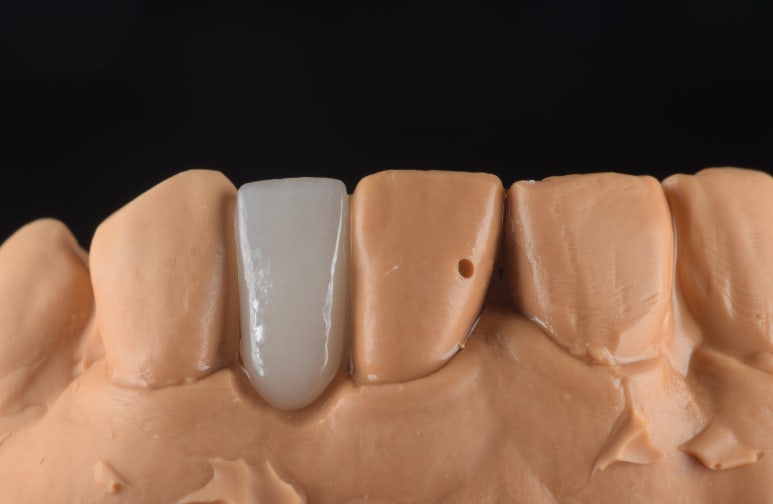

2) 넓은 공간은 메릴랜드 브릿지로

임플란트 대신 선택한 것은

'메릴랜드 브릿지'입니다.

일반 브릿지와 달리 치아를 전체적으로 깎지 않고,

인접 치아 안쪽에 얇은 날개 모양의

보철물을 붙여 치아를 연결하는 방식입니다.

덕분에 소중한 자연치아 삭제량을

획기적으로 줄일 수 있었습니다.

2) 정밀한 기공 제작

기공소장님과 긴밀히 소통하여

환자분의 치아 색상과 투명도를

자연치아와 유사하게 재현한

보철물을 의뢰했고, 정성스럽게 제작된

보철물을 확인했습니다.